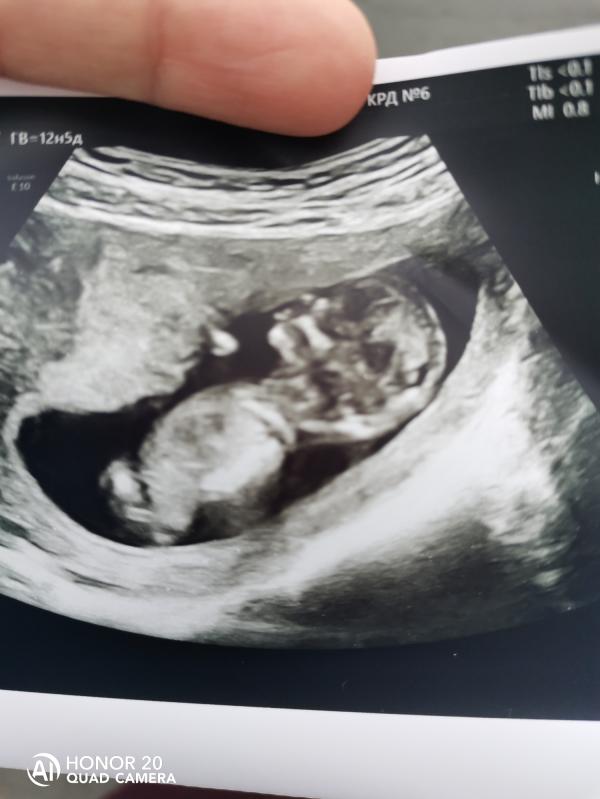

Сегодня была на первом скрининге😍с малышом все хорошо 🙏сказали мальчик😍очень обрадовалась, но узистка сказала что пока рано🥺а так говорит похож на мальчика.

Узи делала в 6 роддоме врач СОНИНА. Л. А